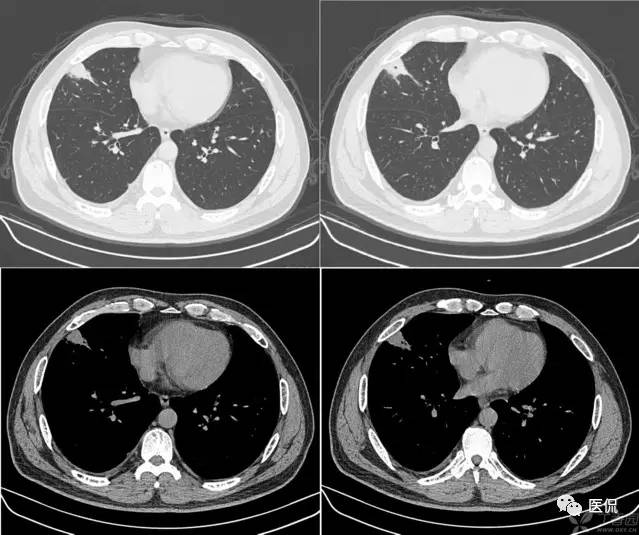

胸腹水鉴别四联症

1、膈肌征:横隔顶向头侧凸出,低密度影在膈外周为胸水,在膈内为腹水。

2、膈脚移位征:胸水时压迫膈脚向前、向外侧移位。

3、界面征:肝与肺在层面上的分界一般是清晰的,腹水时也清晰明确,而当胸水时则肝肺分界不清晰。

4、肝裸区征:肝的背侧内部肝与膈肌直接相贴,此为裸区,产生腹水时液体不在此区潴留。